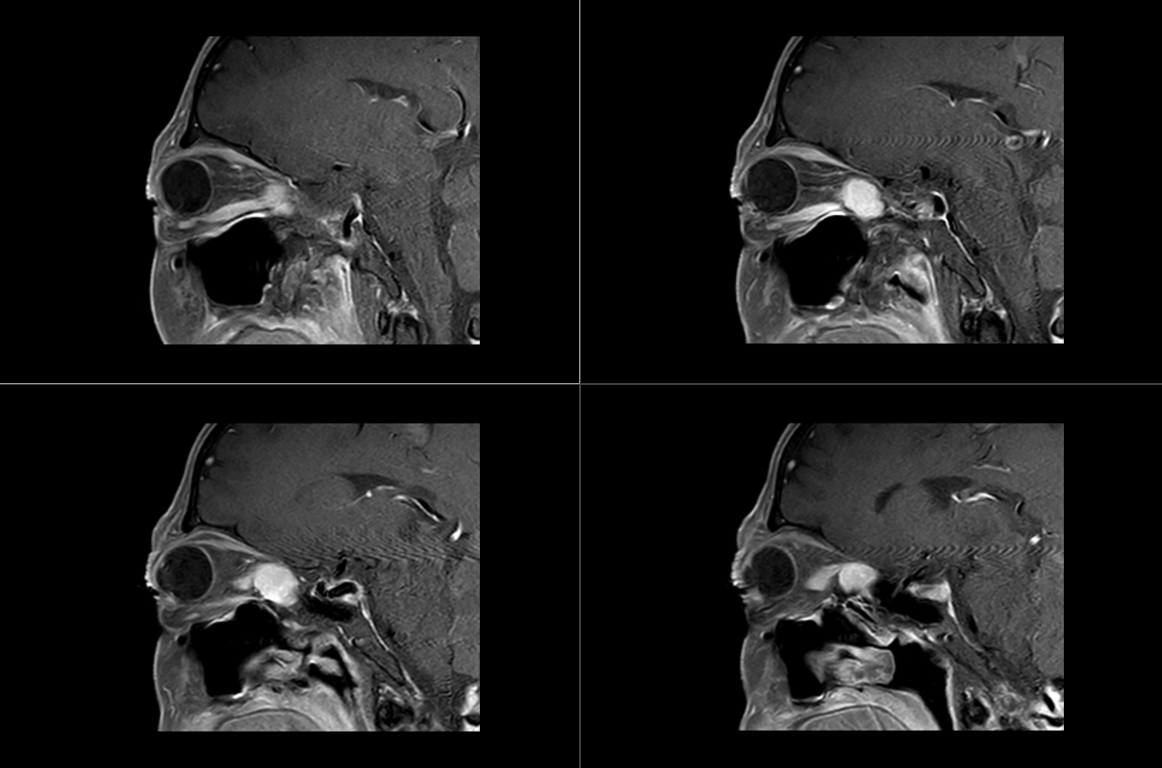

术前影像:

术前影像: